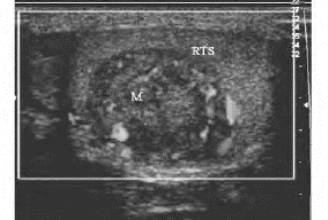

1.患侧睾丸弥漫性或不规则肿大,与健侧不对称,轮廓不整齐,表面不光滑(图31-5)。

图31-5 睾丸肿瘤声像图(见彩图39)

睾丸内低回声包块,CDFI:血流较丰富